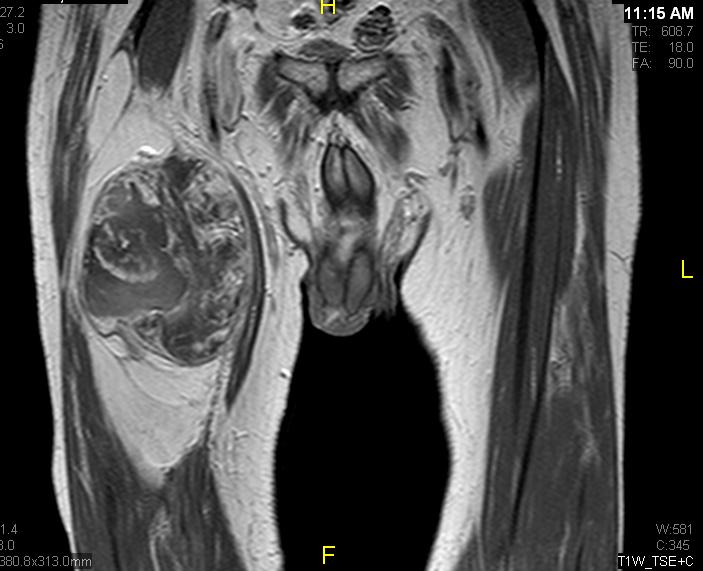

• Large encapsulated lipomatous mass with multiple thick internal trabeculations. (Fig. 1 – 13)

• Signal loss on FS T1 weighted images, and focal nodules(>1 cm is suggestive of a DDLS). (Fig. 1 & 7)

• Contrasted images show hyper-enhancement of the tumors. (Fig. 4, 5, 11-13)

Fig. 7 & 8 Magnetic Resonance Image shows a large heterogeneous mass in the right thigh with low intensity signal on Axial (Fig. 7) and Coronal (Fig. 8) T1-weighted images admixed with high signal areas. The high signal areas represent low grade fatty tissue and low signal the dedifferentiated areas. Higher intensity signal is visible compatible with hemorrhage or necrotic tissue.

Fig. 11 – 13 Axial (Fig. 11), Coronal (Fig. 12) and Sagital (Fig. 13) contrasted T1-weighted MR images show a large heterogeneous mass with central and peripheral

enhancement. Multiple thick trabeculations. Central low signal intensity image is compatible with necrosis and hemorrhage.